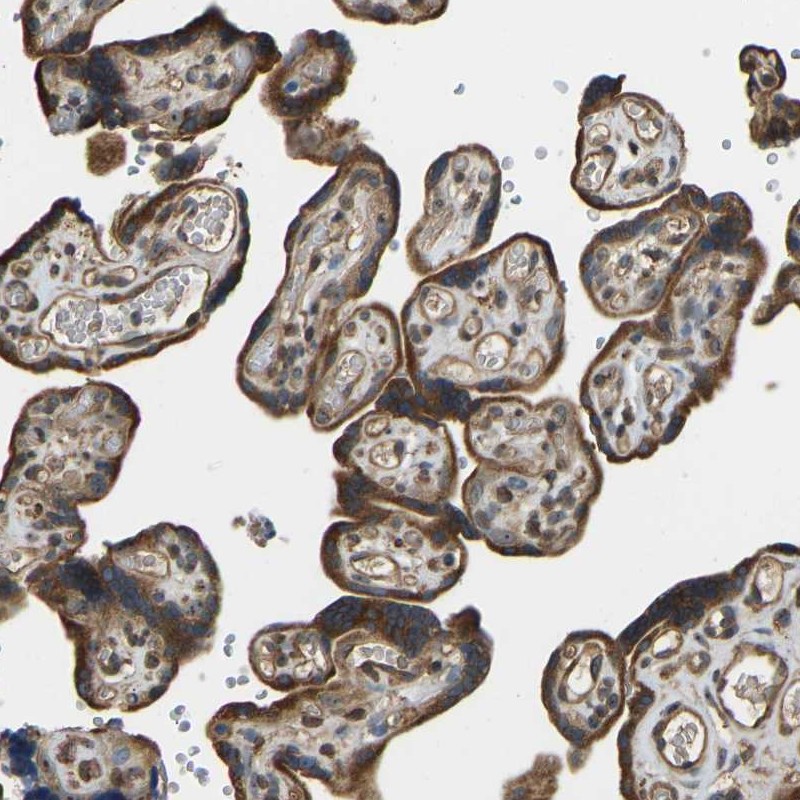

Immunohistochemical staining of human placenta shows cytoplasmic positivity in trophoblastic cells.